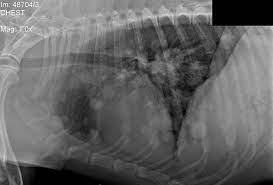

Carcinomas account for 97% of primary lung tumor in dogs with adc more prevalent and scc uncommon. Alveolar pattern observed in metastatic mammary and pulmonary neoplasia is due to confluence of smaller tumor nodules, hemorrhagic or necrotic reaction of lung parenchyma to tumor emboli, pulmonary edema secondary to airway obstruction by tumor, or extension of tumor into alveolar spaces + dogs. The second kind of lung cancer in dogs is called metastatic lung cancer, which means the cancer originated somewhere else in the body, but has spread to the lung. Most dogs with lung tumors present with coughing, exercise intolerance or other respiratory signs. Metastatic spread of primary lung tumors is generally to other areas of the lungs, tracheobronchial lymph nodes, bone, and brain.

The second type is metastatic lung cancer whichis cancer that originates elsewhere in the body such as a leg bone, the mouth, or the thyroid gland, but has spread to the lung via the bloodstream. For example, lung cancer tumor cells that travel to the liver will show up as. Dogs with metastatic lung cancers generally have several tumors in the lungs, not just a single growth. Lung cancer in dogs and cats compared to people, primary lung cancer is very uncommon in dogs. However, primary lung cancers are being seen more frequently over the last 20 years. Adenocarcinoma and alveolar carcinoma are the most common types. The main highways of travel for cancer cells are the bloodstream and the lymphatic system (lymph nodes). Runny nose and runny eyes are possible. The american veterinary medical association (avma) reports that one in four dogs will develop cancer at some time in their life and that 50% of pets over the age of 10 will develop cancer. Primary lung tumors are those that arise from the lungs, mostly from cells lining the bronchi. Lung cancer in dogs can be primary or metastatic. Epithelial lung tumors one of the types of tumors are called epithelial lung tumors. + types of lung tumors.

Lung metastasis in dogs (and sometime it happens to cats, too) is a tough situation to experience. It is even less common in cats. If your dog has metastatic neoplasia, you have to see a veterinary professional to find the primary tumor. Adenocarcinoma tumors in dogs start out as abnormal growths in the epithelial tissue layer. Canine lung cancer is of 2 types: Other less specific signs include fever, lameness, and, in cats, vomiting. There are two type of lung cancer diagnosed in dogs. Lung tumors are considered rare in cats and dogs. The following diagnostics are recommended: This tumor tends to grow as a large, single, and solitary mass, but may spread within the lungs, to local lymph nodes, or even bone. The second kind of lung cancer in dogs is called metastatic lung cancer, which means the cancer originated somewhere else in the body, but has spread to the lung. The most common causes of lung cancer in dogs includes: In both dogs and cats, no consistent breed or gender predisposition is found.